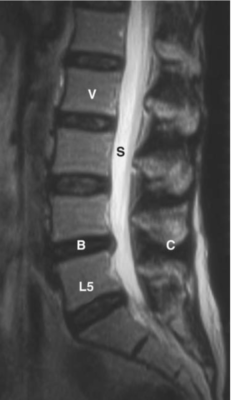

Cột sống thắt lưng

Các chữ viết tắt:

- L5 = L5 vertebral body; thân đốt L5

- N = Nerve root; Rễ thần kinh

- PI = Pars interarticularis; Phần liên mỏm khớp (eo)

- PL = Pedicle; cuống cung

- S = Spinal canal, cauda equina (C); ống tuỷ, đuôi ngựa

- SI = Sacroiliac joint; Khớp cùng chậu

- V =Vertebral body; Thân đốt sống